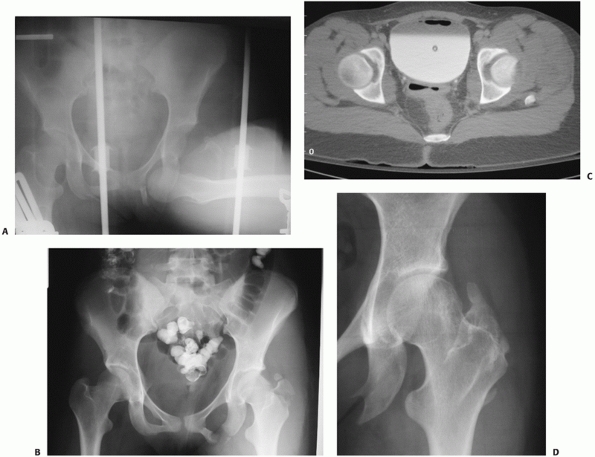

pelvis are obtained. Radiographs should include AP, both Judet

(45-degree oblique) views (Fig. 46-5), and an

inlet and outlet of the pelvis. It is best to focus the beam in the

center of the pelvis, as this allows for a direct comparison of the

affected hip with the normal hip when examining congruence and joint

space. When evaluating each of these views, the first issue is whether

there is a concentric reduction of the hip. The use of the

contralateral hip is necessary to answer this question. The congruence

of the hip is evaluated by comparing the relationship of the femoral

head to the roof on each view and comparing it to the contralateral

side. This relationship should show no loss of parallelism.

Additionally, the joint space should be equal to the contralateral hip.

The CT scan is more sensitive in detecting small intra-articular

fragments, femoral head fractures, femoral head impaction injuries,

acetabular fractures, and joint incongruity.5,36,46,100,119,158,192 It has been demonstrated that intra-articular fragments are better visualized on CT than plain films. Hougaard et al.67

reported six cases of minor acetabular fracture and six cases of

retained intra-articular fragments visualized on CT and not visible on

plain radiographs in patients after closed reductions of posterior hip

dislocations. Additionally, Baird and colleagues5

demonstrated CT to be more sensitive than plain radiographs in

identifying 2-mm methylmethacrylate beads placed in cadaveric hips. The

congruence of the hip is also easily evaluated using CT. The head

should be in the center of the subchondral ring of the acetabulum as it

becomes visible, appearing as a bullseye.173

A difference of as small as 0.5 mm in the distance from the anterior,

articular surface to the femoral head has been reported to indicate a

subluxation of the hip.18 Impaction

![]() |

FIGURE 46-5

A 53-year-old woman with a posterior hip dislocation demonstrating fragments in the joint prior to hip reduction and an inferior femoral head fracture (A). The postreduction AP and Judet views (B-D) demonstrate a widened joint space compared with the normal side and an incongruent reduction. Note that there are fragments both superior and inferior in the joint and that there is a loss of parallelism of the femoral head and acetabular articular surfaces. |